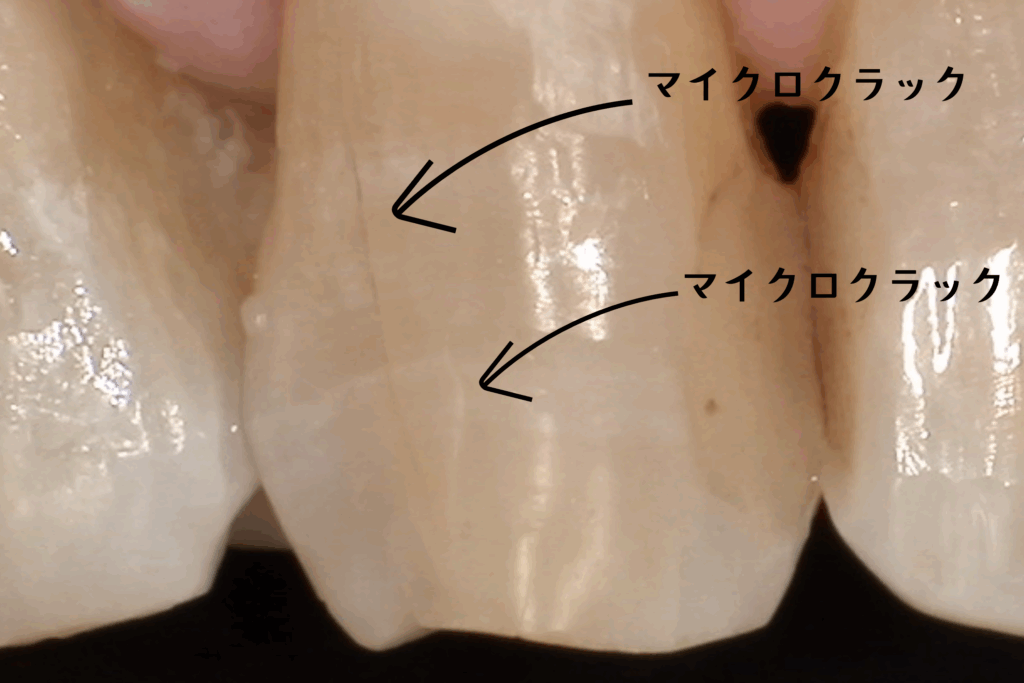

そう驚かれる方がほとんどです。それも無理はありません。なぜなら、このヒビは肉眼ではほとんど見えないレベルの細かさだからです。しかし、この小さな亀裂こそが、将来的に歯を失う原因になりかねないリスクであることを、皆さんに知っていただきたいのです。

1. 肉眼では見えない『マイクロクラック』の正体

毎日食事をし、噛み合わせることで、歯には想像以上の負担がかかり続けています。長い年月をかけて、硬いエナメル質には目に見えないほどの細かい亀裂が入っていきます。これを歯科用語で『マイクロクラック』と呼びます。

年齢とともに増える『歯の年輪』

正直に申し上げますと、マイクロクラックは誰にでもあります。 私たち人間も、年齢を重ねれば肌にシワができるように、歯にも経年変化としてのヒビが入ります。40代、50代と年齢を重ねるにつれ、マイクロクラックの数は確実に増えていきます。これはある種、歯が頑張って働いてきた証(年輪)のようなものであり、すべてのヒビが悪さをするわけではありません。

3. マイクロスコープがないと見えない世界

NK dental TOKYOでは、精密治療のために『マイクロスコープ(歯科用顕微鏡)』を常用しています。 なぜなら、『歯のヒビは、肉眼や一般的な拡大鏡(ルーペ)レベルでは見落とすことが多いから』です。

実際に、原因不明の痛みを訴える患者様の歯をマイクロスコープで拡大し、強い光を当てて観察すると、驚くような光景が見えてきます。 健康そうに見える白い歯の溝に、まるで稲妻のように走る鋭いライン。 染色液を使って染め出すと、そのラインがくっきりと浮かび上がります。

「うわっ、こんなにヒビが入っているんですか…」

モニターでご自身の歯の状態を見た患者様は、皆様絶句されます。 しかし、現状を『視る』ことこそが、治療の第一歩なのです。